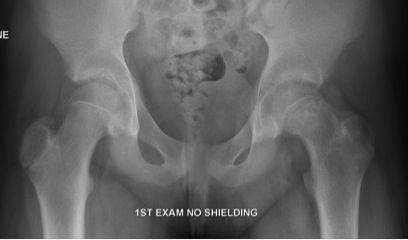

AP

Trethowan Line / Kleins Line

- line along superior neck usually transects 20% head

- originally described as AP but can also be used as lateral

Widened physis

Inferomedial remodelling in chronic slip

Metaphyseal Blanch Sign of Steel

- Increased cresenteric density in the metaphysis due to overlapping of the metaphysis with the epiphysis

Capener's Sign

- the posterior acetabular margin normally cuts the medial corner of the metaphysis

- in a slip the whole of the metaphysis remains lateral to the acetabular margin